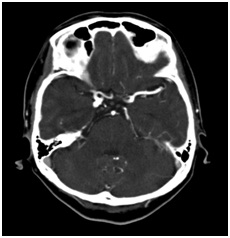

注文割引 腹部、骨盤(CT) 健康・医学の詳細情報

腹部、骨盤(CT)。111A48 | 消化管憩室 国試 | M3E Medical。新しくCT装置を導入しました | 阿蘇立野病院。専用 玄米餅1パック 玄米よもぎ餅1パック。109A35 | 虫垂炎 国試 | M3E Medical。チョロQ zero あぶない刑事 08 日産 セドリック 港7号。。マーカー、折れ等はありません。GE 16列CT BrightSpeed 買取(福岡県) | 中古医療機器の販売。CT室 - 加西市ホームページ。ハリーウィンストン リリークラスターネックレス レディース YG。100A21 | 心臓腫瘍 国試 | M3E Medical。Zig Zag 1 1/4 Ultra Thin Paper Cones (6-Pack)。パラ見程度です。Amazon.co.jp: ボディスカルプチャー BODY SCULPTURE 腹筋。Supria Advance FR | 富士フイルム [日本]。表紙に若干の擦れ傷があります。「腹部のCT」陣崎 雅弘定価: ¥ 13000#陣崎雅弘 #陣崎_雅弘 #本 #自然/医療・薬学・健康